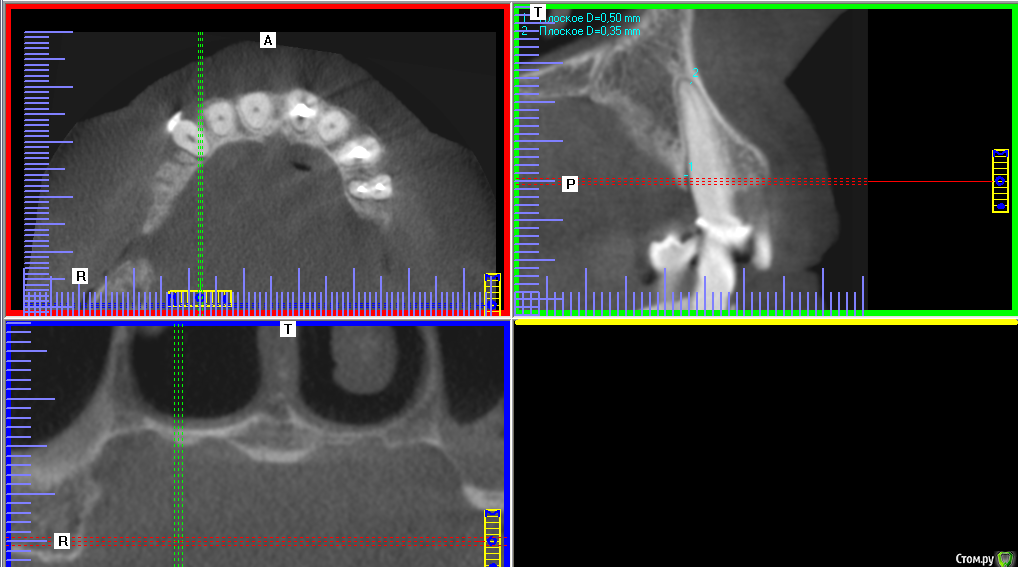

Altai Barnaul Опубликовано 18 декабря, 2017 Поделиться Опубликовано 18 декабря, 2017 Здравствуйте! Что видно на снимке?Сколько пародонтальных карманов? Спасибо. 1 Ссылка на комментарий

DmitrySH Опубликовано 18 декабря, 2017 Поделиться Опубликовано 18 декабря, 2017 Снимок не информативен, панорамный снимок есть? Ссылка на комментарий